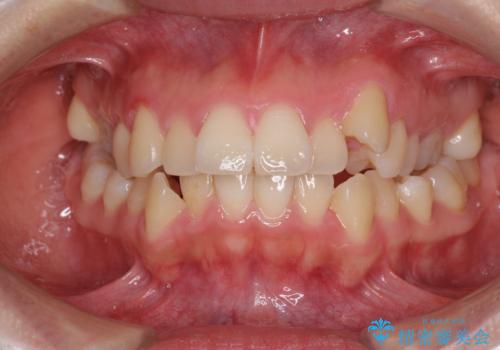

閉じにくい口元と八重歯 ワイヤー装置での抜歯矯正

見えないほど重なっている前歯 抜歯矯正でスッキリとした歯並びに